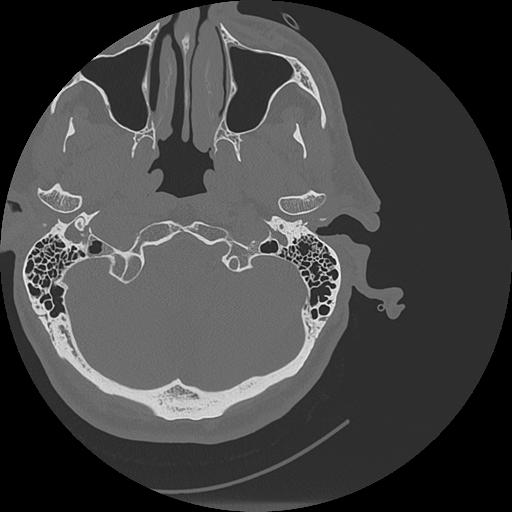

7 HUESO,,Vol,0.5,HUESO,,